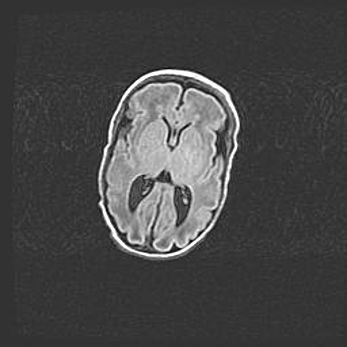

Множественные кисты обоих полушарий головного мозга, наибольшая из них в правой затылочной области. Ассиметричная атрофическая гидроцефалия.

Возраст: 7 месяцев

Вес: 5660 г

Пол: мужской

Окружность головы: 41,5 см

Срок гестации: 28-29 недель

Кисты головного мозга развиваются в результате многоочаговых некрозов вещества мозга и возникают вследствие перенесенной перинатальной инфекции, менингитов, энцефалитов, асфиксии, родовой травмы, расстройств мозгового кровообращения различного генеза. Образованию кист в веществе головного мозга плодов и новорожденных способствуют такие факторы, как высокое содержание в нем воды, недостаточная (или отсутствие) миелинизация и слабая астроглиальная реакция на повреждение.

Кисты могут сочетаться с гидроцефалией и другими поражениями головного мозга.